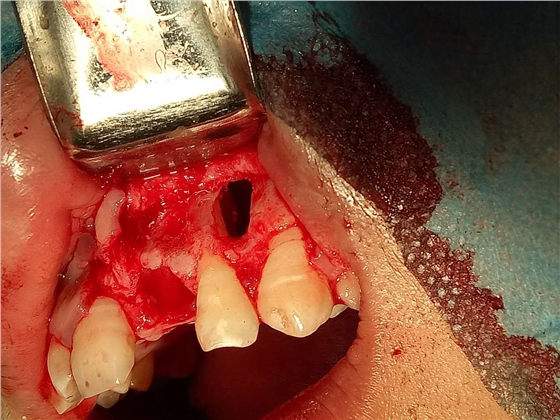

死髓牙2度,沒保留價值了,外傷造成的外吸收,即使到充也容易出問題。和患者溝通,要求做種植,用了兩個骨膠原,側切、尖牙沒事,側切做了一次根充